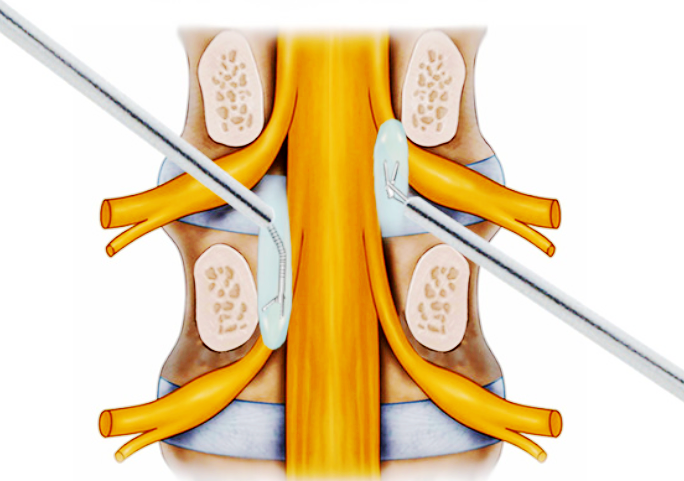

解剖示意图

经椎间孔入路内镜手术(percutaneous endoscopic lumbardiscectomy ,PELD)是目前最微创的脊柱手术之一,可在直视下摘除突出髓核,避免组织结构损伤,从而保留原有正常的结构与功能。

椎间孔镜示意图